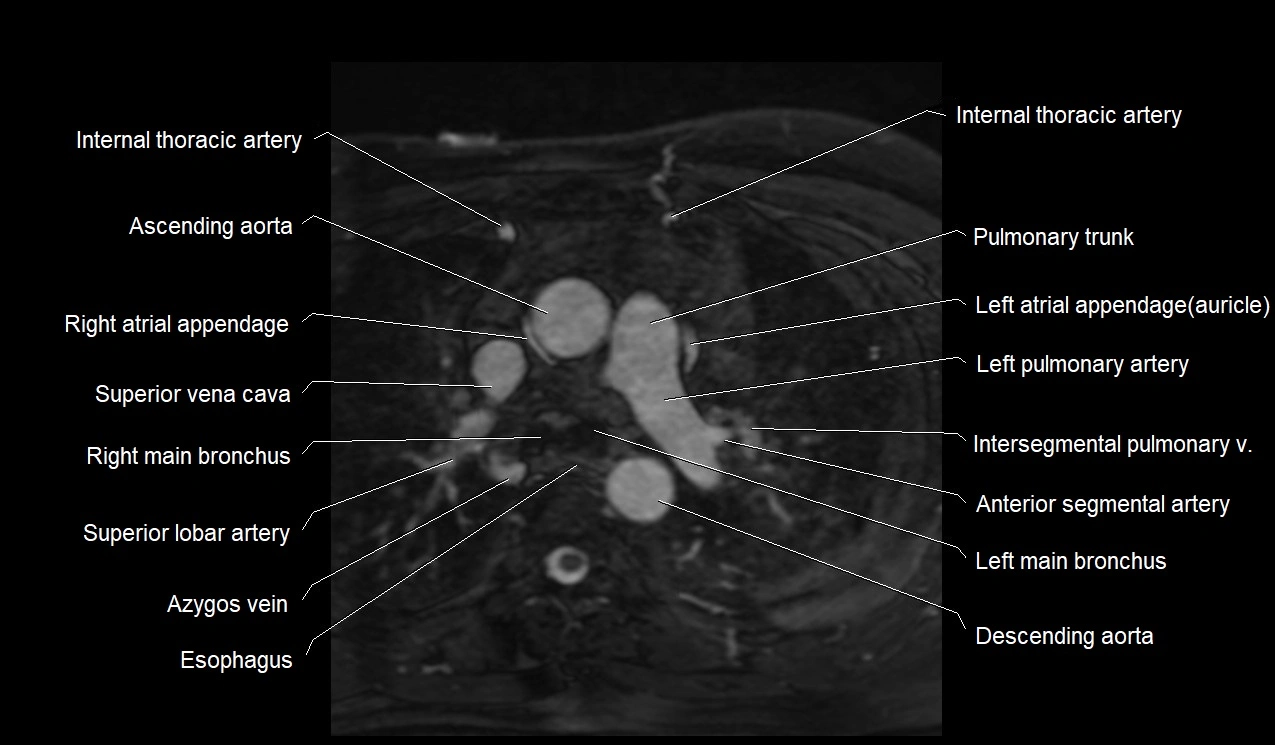

MRI image